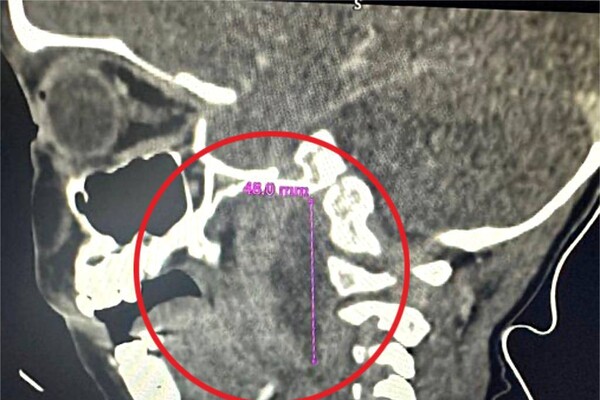

В больницу пациент поступил с выраженным отеком шеи и температурой до 39°C. Родители мальчика рассказали, что ребенок уже неделю болел ОРВИ. Они лечили его жаропонижающими самостоятельно, но это эффекта не давало. Медики провели обследование и установили, что у ребенка развился гнойный абсцесс в шее как осложнение перенесенной инфекции.

«Гнойный абсцесс в области шеи очень опасен, так как может привести к сужению дыхательных путей, повреждению сосудов и нервов, тромбообразованию и даже параличу», — рассказала заведующая оториноларингологическим отделением Елена Ковалец.

Мальчика доставили в ЛОР-отделение, где провели ему экстренную операцию по удалению гноя.